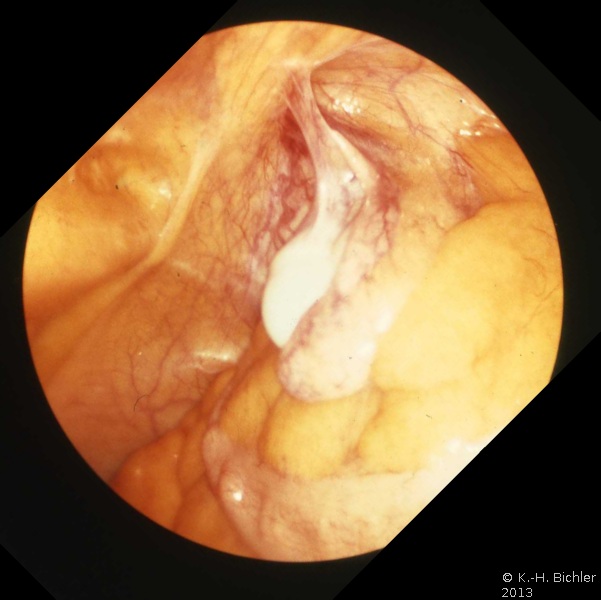

Von hoher Aussagekraft, die sogar MRT übertrifft, ist die diagnostische Laparoskopie. Castilho fand durch diagnostische Laparoskopie 60% der dystopen Hoden, in 40% fehlte das Organ (Dysgenesie)

Literatur:Castilho, L.N.: "The Effectiveness of Diagnostic Laparoscopy as an Alternative to Exploratory Surgery for Nonpalpable Testes", Medical Care International, Mai-Juni 1992

Die Abbildung zeigt die laparoskopische Darstellung eines atrophischen Bauchhodens bei einem 25 Jahre alten Mann (Abbildung 5). Die Atrophierate des Bauchhodens beträgt bis zu 20%.